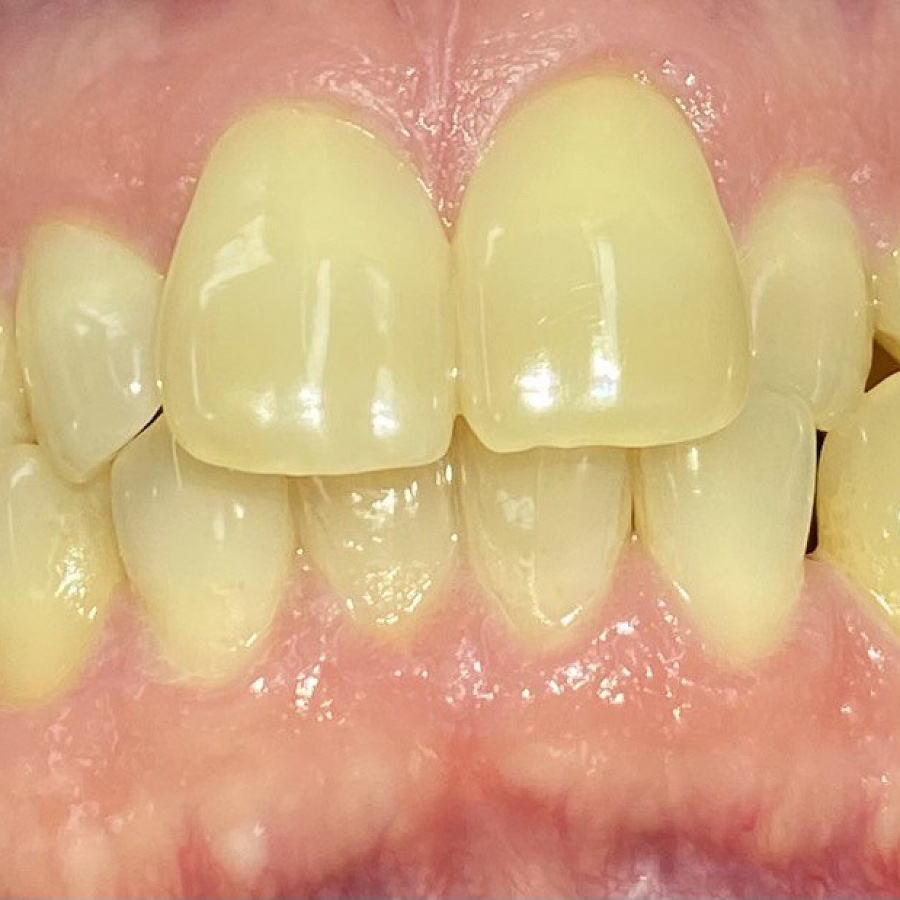

Обращение пациента

С какой проблемой обратился пациент

Пациент обратился с жалобами на неровные передние зубы верхней и нижней челюстей.

Какой диагноз поставили

Диагностика показала:

• сужение зубных рядов,

• обратное перекрытие в области фронтальных зубов слева,

• разворот по оси передних зубов верхней и нижней челюстей,

• стираемость эмали зубов,

• индивидуальную микродентию 12 и 22 зубов.